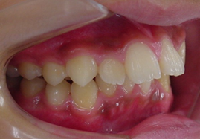

初診時

治療途中

終了時

当矯正歯科医院ではMEAW法(マルチループ)で治療する事で非抜歯で治療しています。

MEAW法(マルチループ)を利用することで以下の様に上顎前突が改善されていきます。